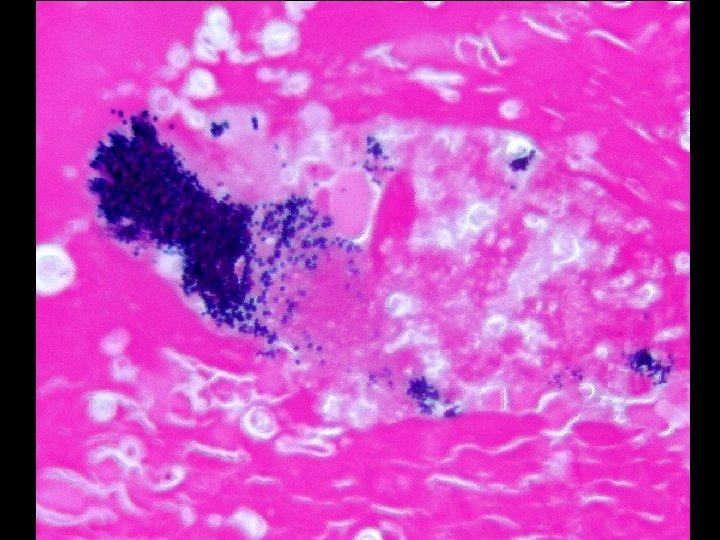

Canine Cases • Intra-lenticular bacteria – 7 negative of H+E and gram stain – 22 positive for bacteria • 19 gram positive cocci • 2 gram positive rods • 1 gram positive cocci and rods

Feline Cases • Duration (2 unknown) Known Cat Scratch Unknown Total < 1 week 0 0 0 1 week- 1 month 2 3 5 1 -4 months 0 4 4 • Intra-lenticular bacteria – – – 4 negative of H+E and gram stain 4 gram positive cocci 1 Candida 1 gram positive and negative bacilli 1 gram positive cocci, gram positive and negative bacilli